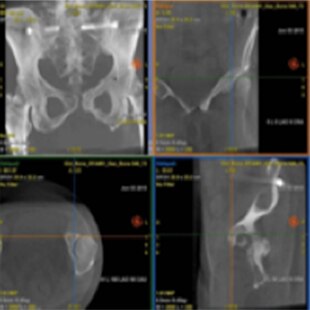

INTERVENTIONS OSSEUSES

Planifier

Guider

Évaluer